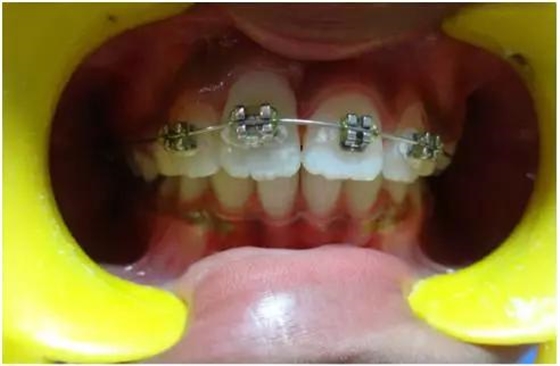

正畸牽引5周后,牙齒復(fù)位到其原始位置,與其他切牙完全對齊(圖3)。開始嘗試血運(yùn)重建。重新打開根管,使用次氯酸鈉和生理鹽水沖洗。然后插入無菌根管銼,并將其推到根尖處,以使血流進(jìn)入根管。一旦血液到達(dá)釉牙骨質(zhì)界,放置一個濕潤的無菌棉球靜置15分鐘,直到血凝塊形成,再放置約2-3mm的MAT在血凝塊上。在MAT上覆蓋一個濕棉球,隨后進(jìn)行臨時修復(fù)。以后再替換為玻璃離子水門汀墊底和復(fù)合樹脂修復(fù)。復(fù)診時間為1、3、6、9和12月。正畸復(fù)位保留12周。然而,在這么長的保留期內(nèi)還是復(fù)發(fā)了錯位,這也強(qiáng)調(diào)了在嚴(yán)重侵入的情況下長期復(fù)位的重要性,因?yàn)槔奂暗难例X周圍出現(xiàn)大量的牙槽骨喪失(圖 4)。

牙齦: 即使病人保持良好的口腔衛(wèi)生,在正畸治療完成后,在受累的牙齒上能觀察到明顯的牙齦萎縮。系帶附著位置可能是原因之一。修整系帶可能可以解決這個問題(圖4)。在軟組織愈合后,復(fù)發(fā)的牙齒復(fù)位至正常位置(圖 5)。經(jīng)過6周病人細(xì)致的口腔衛(wèi)生維護(hù),牙齦狀況和美觀得到改善(圖6和7)。

結(jié)果及隨診

隨訪12個月的X線記錄顯示:在年輕恒切牙的根管壁上有硬組織沉積。從長度上看,牙根并沒有繼續(xù)發(fā)育,但根尖處硬組織沉積,而且?guī)缀蹰]合了(圖 8)。

12個月后,對牙11進(jìn)行活力測試表現(xiàn)出輕微的陽性反應(yīng),建議繼續(xù)觀察看看血運(yùn)重建是否成功。熱/冷敏試驗(yàn)和電活力測試顯示均為陰性,表明牙髓神經(jīng)沒有再生。然而,只有在牙齒出現(xiàn)臨床上或影像學(xué)提示發(fā)生感染的情況下,才需要進(jìn)行根管治療。此外,牙齒變色和透明度改變的問題沒有得到改善,這會影響美觀,需要將來進(jìn)行干預(yù)。

牙12 顯示根尖完全閉合,牙髓活力測試陽性,提示已成功恢復(fù)。

牙11在進(jìn)行修整系帶后,牙齦外形得到改善,但是仍然可觀察到輕微的牙齦萎縮,可能因?yàn)槔奂把赖难啦酃菃适А?/span>